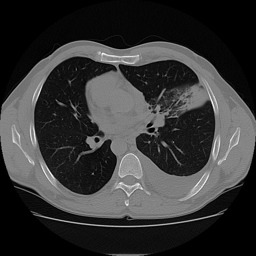

One of these is fake, and you can probably already tell which one it is.

Recently, I have been leading a small team of 3 students at Georgia Tech in a project to explore the use of generative models for privacy-preserving image generation for CT slices of patients' lungs. We are specifically participating in the ImageCLEF 2026 ImageCLEFmed GANs competition Subtask 3 "Privacy-preserving CT slice generation". In this post we will go over some exploratory data analysis on the 2025 dataset. Unfortunately, the 2026 dataset was not available at the time of presenting our results for the EDA work. We were able to acquire the 2025 data and perform some preliminary analysis with the overarching goal being to determine if the 2025 generated dataset was privacy-preserving.